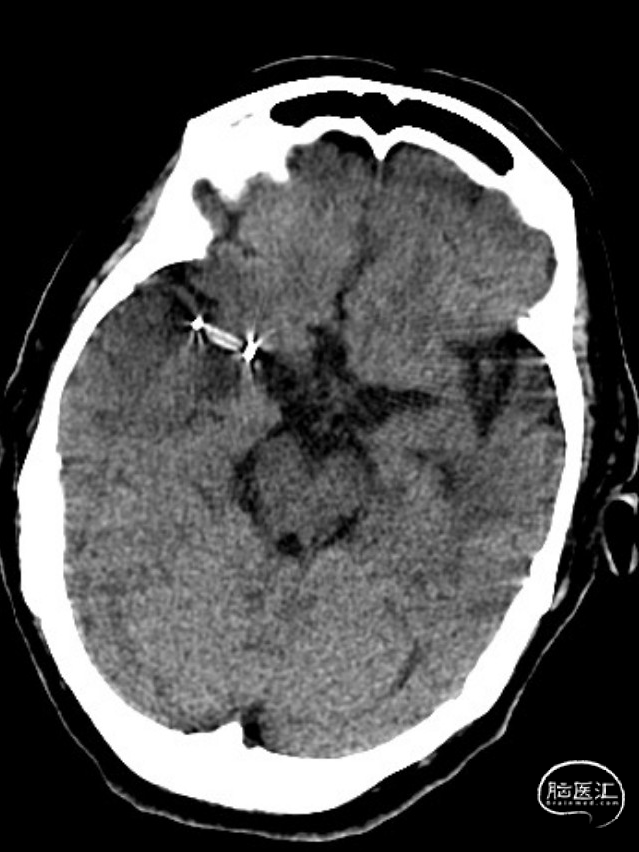

术后第一天复查颅脑CT未见异常染色及大面低密度病灶。

查头颅MRI:右侧基底节区、右侧顶颞岛叶急性脑梗死。

神经系统查体:神志清楚,言语稍含糊,双侧瞳孔等大等圆,直径3mm,对光反射灵敏,左侧鼻唇沟浅,伸舌偏左,四肢肌张力正常,右侧可抬举,肌力查体欠合作,左上肢4级,左下肢3级,左侧巴氏征阳性;双侧针刺觉未见明显异常,双侧指鼻、跟膝胫欠合作;颈软,脑膜刺激征阴性。NIHSS:4分。